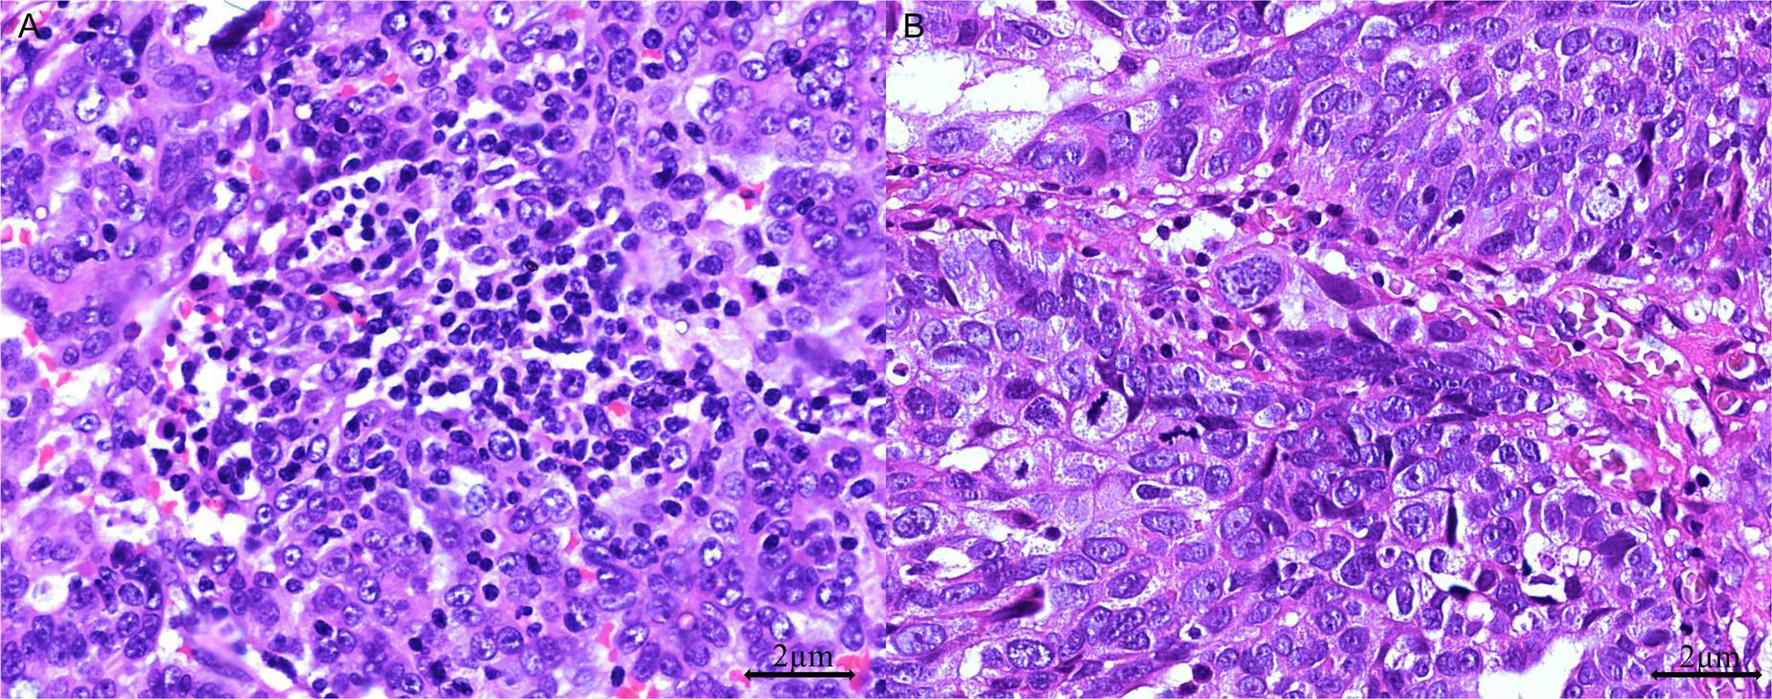

Areas with the highest concentration of TILs or mitotic figures, termed “hot spots,” were identified for evaluation. Mononuclear cells were considered TILs when located within the tumor margins or in the intercellular spaces and the cores of papillary tumor structures. Cells outside the tumor border, those associated with necrotic regions, and those within blood vessels were excluded. TILs were considered positive when the tumor contained more than 40 intraepithelial lymphocytes in at least one high-power-field (HPF) (Figure 2). Furthermore, we classified mitotic activity using the Nottingham Grading System (32), which was originally developed for breast cancer histopathological grading. Using our microscope (Olympus BX43) with a 0.5-mm field diameter, we counted the number of mitotic figures in 10 consecutive HPFs within the most mitotically active area of the tumors and subsequently categorized tumors as low (≤ 7 mitotic figures/10 HPFs), moderate (8–14 mitotic figures/10 HPFs), or high (≥ 15 mitotic figures/10 HPFs) (33).

FIGURE 2

Tumor-infiltrating lymphocytes (TILs) in HGSOC. (A) TIL-positive: > 40 dense intraepithelial infiltrates of TILs (H&E stain, 400 × magnification); (B) TIL-negative: ≤ 40 sparse infiltrates of TILs (H&E stain, 400 × magnification).